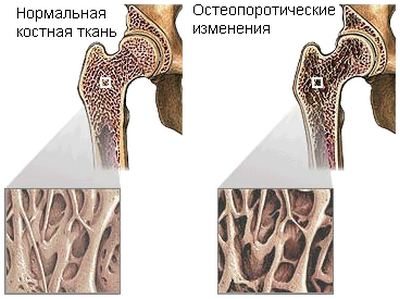

Сначала о том, что такое остеопороз. Остеопороз — прогрессирующее уменьшение плотности костной ткани. Потеря кальция приводит к тому, что кости становятся чрезвычайно хрупкими и могут сломаться даже при пустяковых «происшествиях». Например, толкнули слегка или автобус резко затормозил. Человек с остеопорозом ударился — и пожалуйста, перелом.

Хуже всего приходится пожилым людям. У них возрастает опасность сломать шейку бедра — довольно тонкую кость в бедренном суставе. А это зачастую означает малоподвижность, операцию, инвалидность и даже смерть от застойных явлений. Только четверть сломавших шейку бедра возвращаются к более или менее нормальной жизни.

Явных симптомов развивающийся остеопороз не дает. Обычно человек узнает о нем, когда неожиданно легко сломает руку или ногу. Тогда он обращается к врачам — хирургу, травматологу или ортопеду. Но гораздо легче предупредить заболевание: следить за весом, уменьшить потребление алкоголя, кофе, мясных продуктов, соленых блюд, отказаться от энергетических напитков.